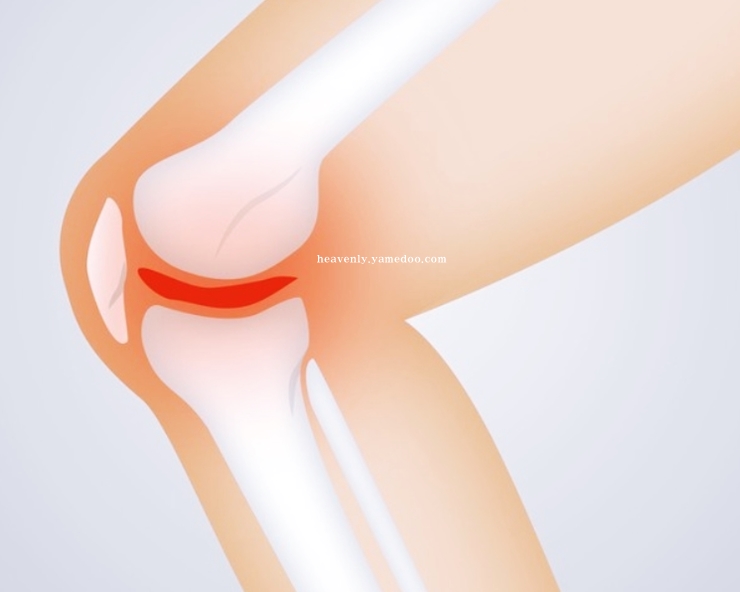

반월상 연골판이란, 무릎 관절 사이사이에 있는 반달 모양의 물렁뼈입니다. 우리의 체중을 견디는 작용을 하는 부위입니다. 무릎 안쪽과 바같쪽에 양쪽에 하나씩 있습니다. 뼈와 뼈가 부딪힐 때 손상되지 않도록 하거나 완충효과를 가지고 오는 것이 바로 반월상 연골판입니다.

무릎에서 쿠션 역할을 하는 반월상 연골판이 파열되면 뚝뚝하고 무릎에서 소리가 나게됩니다. 또 무릎이 삐걱대거나 뻑뻑한 느낌이 듭니다. 반월상 연골판에 문제가 발생하면 조금만 걸어도 통증이 나타나고 경사로 또는 계단을 오를 때 갑자기 다리에 힘이 풀려 주저앉는 일이 발생할 수 있습니다.

만약 연골판 손상을 방치하면 퇴행성 관절염으로 발전할 수 있습니다. 반월상 연골판이 제 역할을 하지못해 각종 부위에 손상이 발생되면 무릎에 있는 관절을 보호하는 기능을 하지 못해 무릎을 구부리거나 움직일 때 심한 통증을 초래하기 때문입니다. 반월상 연골판의 중요성을 다시 한 번 깨닫게 되었습니다.

무릎통증 원인 초기에는 단순한 타박상으로 오인할 수 있습니다. 그런데 치료하지 않고 방치하면 뼈와 뼈가 서로 맞닿으며 퇴행성 관절염을 불러옵니다. 반월상 연골판은 혈관이 존재하지 않아 한 번 손상되면 자연적인 치유 또는 재생이 어렵운 신체부위입니다.